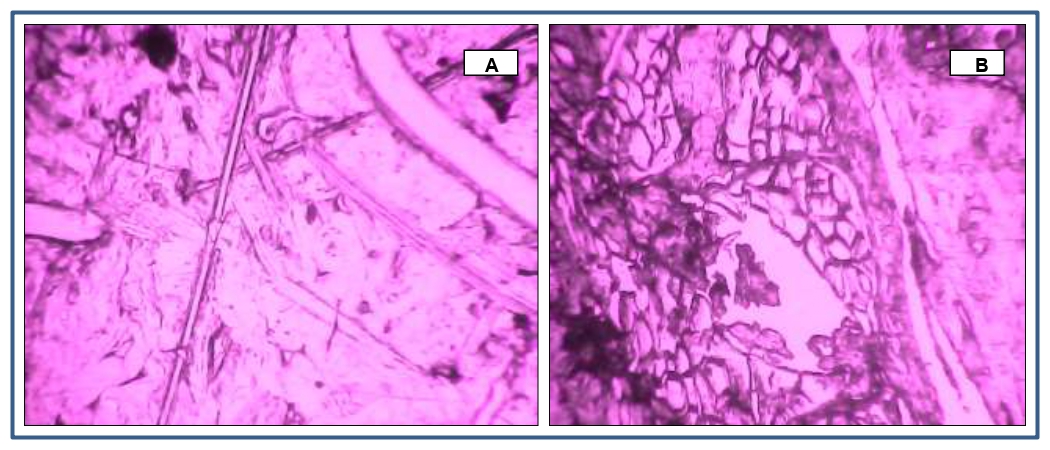

The flux was used to gauge the permeation of TA through the skin. Highest flux was obtained for the batch 2% hydrogel formulation in comparison to the pure drug penetration enhancers. The molecular size and lipophilic nature of complex produced maximum flux by maximizing the amount of free TA available for permeation. The hydrogel formulation showed the release of 87.52% at the end of 9h. In vitro drug release of pure gel was 70.23±0.07% within 9 h. It was observed that the NLC hydrogel shows flux was higher compared to the other formulations. The 2% batch shows that permeability coefficient and Flux(J) were 0.0155 and 5.455±0.43 respectively. Histological study of permeation of pure drug gel (A) and 2% hydrogel (b) magnification at 40X shown in fig. 6.

Fig. 6: Histological study of permeation of pure drug gel (A) 2% hydrogel magnification at 40X